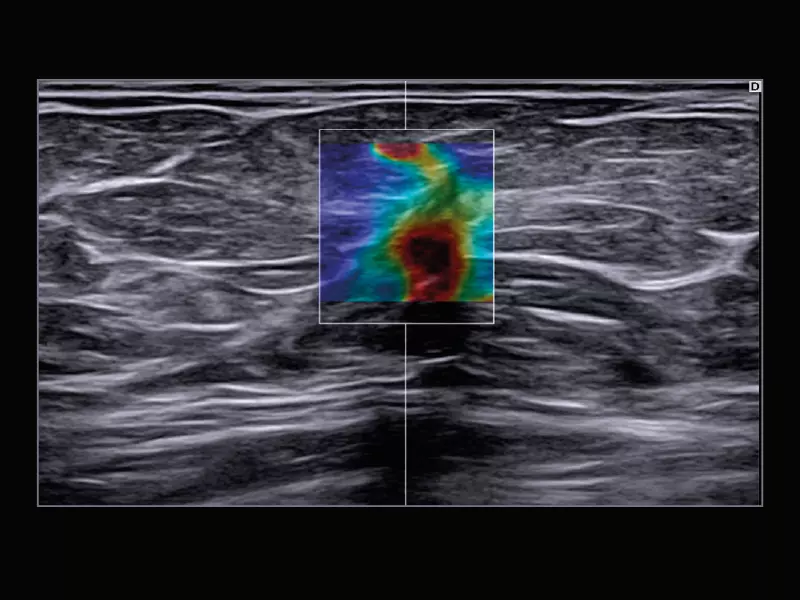

MyLab™C30 - SWE breast

MyLab™C30 - SWE breast